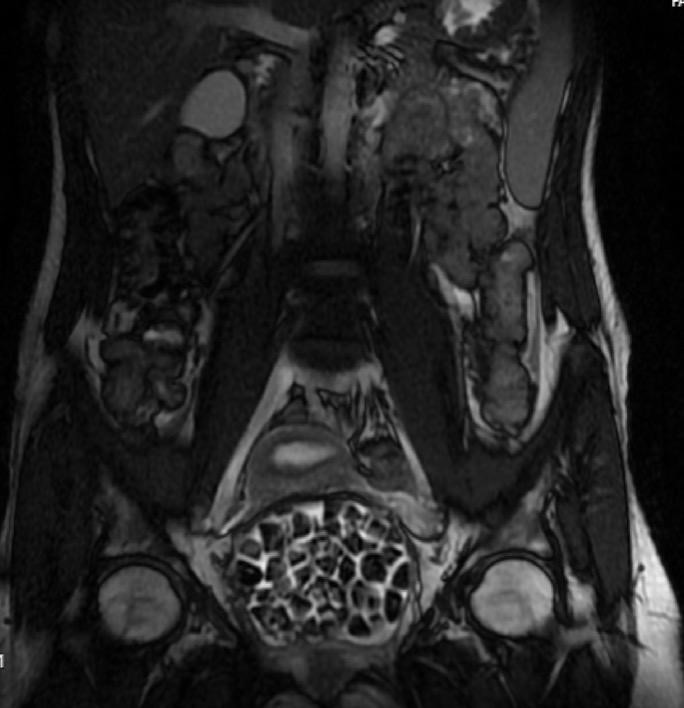

Hastasının durumunu değerlendiren Üroloji Uzmanı Doç. Dr. Erkan Erkan, "Hastamızın 2004 yılında doğduğunu ardından doğar doğmaz ekstrofi vezika dediğimiz 50 binde bir görülen bir anomaliden dolayı art arda ameliyatlar geçirdiğini öğrendik. 10 yaşında yine bir ameliyat geçirmişti, gerekli görüntüleme ve tetkiklerimizi yaptırdık. Normalde mesanesinin olması gereken yerin hemen arka kısmında taşlarla dolu bir kese olduğunu gördük, bunun üzerine ek görüntülemeler; MR çektirdik. Hastamız çelişkili açıklamalar almıştı, kendi radyolojik kliniğimiz ve edindiğimiz konsültasyonlarda taşların mesanede değil vajinal boşlukta oluştuğunu düşündük, bir planlama yaptık.

Genç kızın uzun süredir karın ağrısı çektiğini belirten Jinekolojik Onkoloji Uzmanı Op. Dr. Emin Erhan Dönmez, "Mesane taşları olduğu düşünülerek daha büyük bir hastaneye refere edilmiş. Aramızda mini bir konsey yaparak muayene ettik. Vajen bir hazne görevi görerek orada durağan bir idrar, uzun süre beklediği için idrar içindeki minerallerde çökerek taşlar oluşmuş. Mesanedeki idrarın vajene akmış olabileceği ve vajende göllenen idrar nedeniyle taşların burada oluşacağını düşündük, ameliyatımızı planladık. Ameliyata tanı amaçlı girmiştik, sistoskopi (Mesane gibi idrar yollarını kapsayan kısımlardaki rahatsızlıkların teşhis ve tedavisinde kullanılan endoskopik bir yöntem) dediğimiz ameliyatı Erkan Hocam ile birlikte gerçekleştirdik.

Önce mesaneyi bir görüntüledik, mesane tabanına yaklaşık 2-3 cm’lik bir alandan vajene fistülize olduğunu gördük. Mesaneden vajene geçtiğimiz esnada tüm vajenin taşlarla dolu olduğunu gördük. Tanı amacıyla girdiğimiz ameliyatta her şey de olağan gittiği için tedaviye geçtik. Taşların çıkabileceği kadar bir genişlik sağladık. Daha sonra yaklaşık en büyüğü 2,5 cm boyutlarında olan, irili ufaklı 287 tane taşı ameliyat esnasında çıkarmış olduk. Taşların tekrarlamaması için idrarın göllenmemesi, en azından dışarıya rahatça boşalabilmesi için vajinal rekonstrüksiyonu sağladık. Ameliyatta da herhangi bir problem yaşamadık. Literatürü Erkan Hocam ile birlikte değerlendirmiştik. Primer olarak vajende birikmiş olan bu kadar çok sayıda taşla ilgili bir makale görmedik, rastlamadık" dedi.